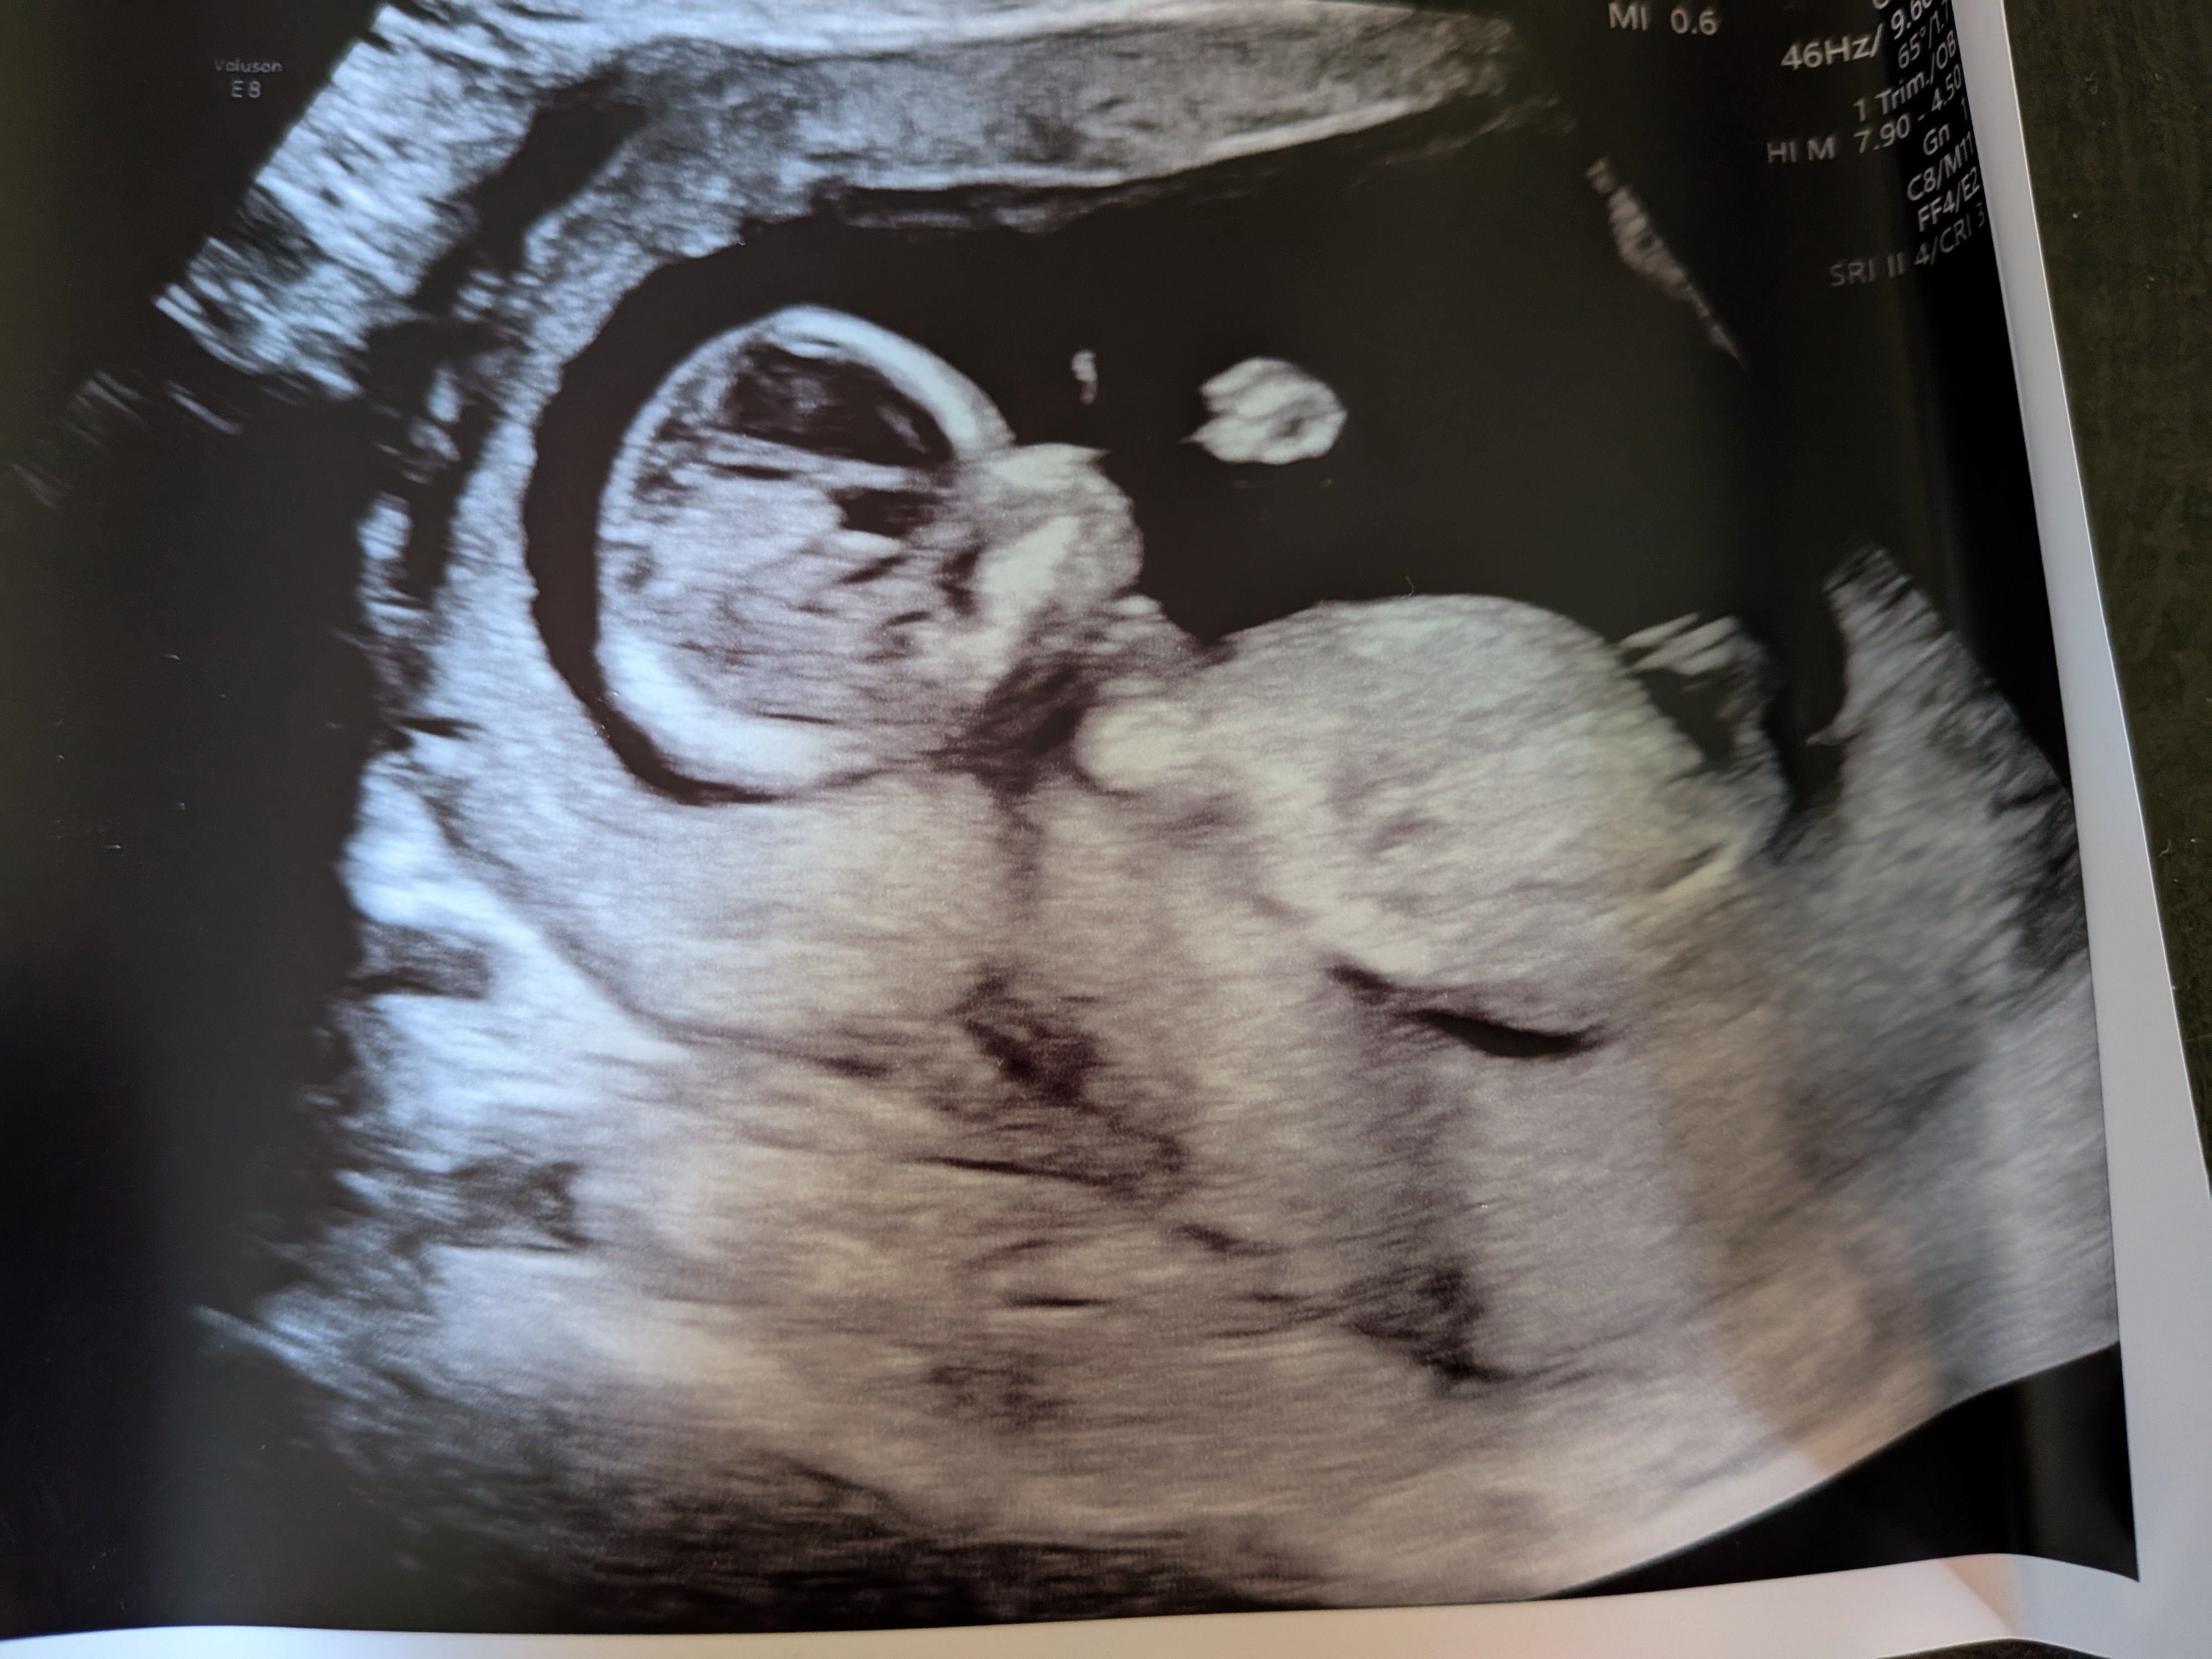

Mannen tenkte feil (selv om han sa kl høyt) og vi endte opp på sykehuset 1 t før OTUL. Utforsket bygget imens. Plutselig fikk jeg sms om at det var min tur! :oops: Viste seg at hun som hadde timen før meg satt fast i kø, så da fikk jeg hennes. Flaks da! Rakk såvidt å bli nervøs. Pratet litt før timen, om forrige fødsel og evt. oppfølging nå, får vite mer om det på OUL. Før vi begynte var hun veldig klar på at man ikke får vite kjønn. Vi sa det går heelt fint, vi er ikke opptatt av det. Jeg syns egentlig folk er litt for opptatt av kjønn :bag: Det syns hun var forfriskende! Også sa hun "eg seie alltid han pga. dialekt". Vi snakket litt videre om datteren vår ila. timen, og etterhvert begynner hun å si "ho" - hun skyldte fort på at det var pga. vi har jente fra før, men lurer på om hun forsnakket seg der :p Anyway, vi så med én gang at det var en frisk og superaktiv krabat inni der! Den hoppet og turnet og snurret rundt - med boksenever foran ansiktet :laughing002 Skulle ikke drukket de slurkene med red bull, for det var vanskelig å få målt :smiley-ashamed004 Men det gikk etterhvert, fikk akkurat nakkefolden til slutt. Ble mange bilder også, inkl. i 3D! Alt så veldig bra ut. Så ingen nub, men jeg kan ikke de greiene uansett. Men basert på at jeg ikke så en penis og en potensiell forsnakkelse lurer jeg på om det blir ei jente til :joyful: Jeg hadde jo egentlig lyst på gutt, men kjenner ikke på noen skuffelse der, selv om det ikke er sikkert ennå. Holder forresten mistanken min privat, for kjente jeg ble litt irritert at alle drev og spurte etter kjønnet etter jeg snappet om vellykket UL :rolleyes: Det er ikke viktig! Senere gikk jeg forbi en Brando Kids og fant ei kasse med ull til 50%, så kjøpte noen plagg i 50-56 :D Det var for det meste "jentefarger" men det driter jeg i :wacky: Fikk btw OUL den 17.09. (18+2)!